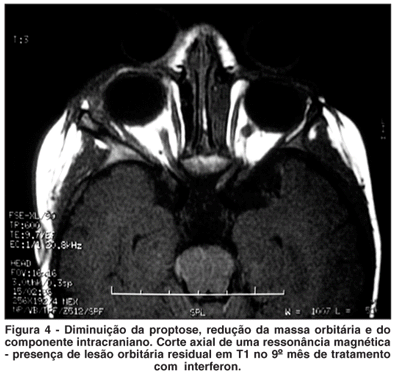

Houve importante melhora clínica (Figura 3) e o exame de ressonância magnética de órbita, durante o tratamento com interferon alfa, apresentou acentuada redução das dimensões da lesão (Figura 4).